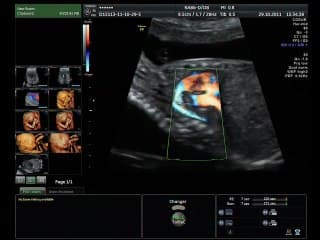

Principes, faisabilité et premier résultats en imagerie de fusion IRM et échographie pour le dépistage et le diagnostic prénatal.Présentation avec films et animations.